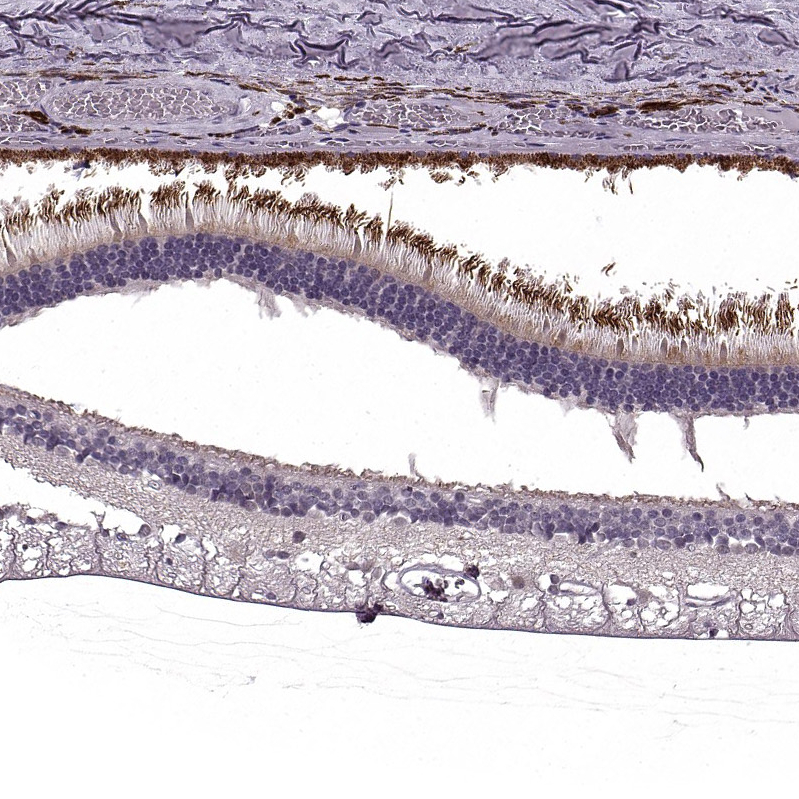

Immunohistochemical staining of human cerebral cortex, eye, retina, liver and lymph node using Anti-RP1L1 antibody HPA024744 (A) shows similar protein distribution across tissues to independent antibody HPA024686 (B).